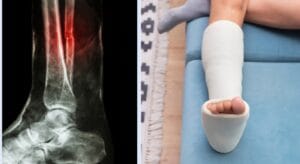

Mức độ 3: Đứt hoàn toàn dây chằng (nặng)

2. Triệu chứng

- Đau dữ dội ngay khi chấn thương xảy ra, có thể nghe thấy tiếng “rắc”.

- Sưng to nhanh chóng, bầm tím rõ rệt.

- Mất hoàn toàn khả năng giữ vững khớp.

- Không thể đi lại hoặc cử động khớp bị tổn thương.

3. Điều trị

Với chấn thương dây chằng mức độ 3, cần can thiệp y tế chuyên sâu:

- Chụp MRI để đánh giá chính xác vị trí và mức độ đứt.

- Phẫu thuật nội soi tái tạo dây chằng là phương pháp phổ biến, đặc biệt ở khớp gối. Có thể dùng gân tự thân (gân bánh chè, gân cơ đùi sau) hoặc gân đồng loại.

- Sau mổ, người bệnh cần tham gia chương trình phục hồi chức năng kéo dài 3–6 tháng. Gồm các bài tập tăng sức cơ, lấy lại biên độ vận động và khả năng kiểm soát khớp.